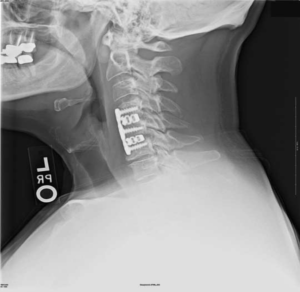

Импланты шейного отдела позвоночника на рентгене.

Если клиника симптомов не поддается консервативной терапии или неинвазивные способы не могут быть задействованными ввиду сильно прогрессирующего стеноза, назначается операция. Вмешательство предполагает использование декомпрессионной ламинэктомии под общим наркозом. При комбинированной проблеме, например, вместе с грыжей, ее сочетают с микродискэктомией и спондилодезом. При спондилодезе осуществляют скрепление смежных позвонков металлическими фиксаторами (стержнями, пластинами, крючками и пр.), установку межтеловых имплантатов или вживление костного трансплантата с металлической гильзой.

Установка металлической конструкции.